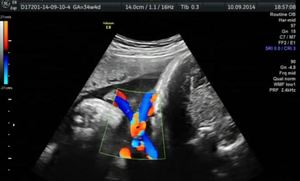

Диагностика патологии

Как видно, обвитие пуповиной шеи плода в большинстве случаев не представляет непосредственной угрозы для жизни ребенка. Тем не менее, всегда лучше быть на чеку и подготовленным к различным сценариям. Поэтому акушеры регулярно проводят обследования беременных женщин, начиная с 32 недели беременности. Для выявления возможных патологий используются следующие методы:

- УЗИ. Это исследование помогает различить истинное обвитие пуповиной от ложного. Врач может определить, обвивает ли пуповина шею плода или просто плотно к ней прилегает.

- Допплерометрия. Этот специализированный вид ультразвукового исследования позволяет оценить скорость кровотока и состояние сосудов плаценты.

- Кардиотокография. Данный метод исследования помогает оценить работу сердца и сосудов плода.

Использование этих методов дает возможность врачам обеспечить безопасные роды даже в случае обвития пуповиной.